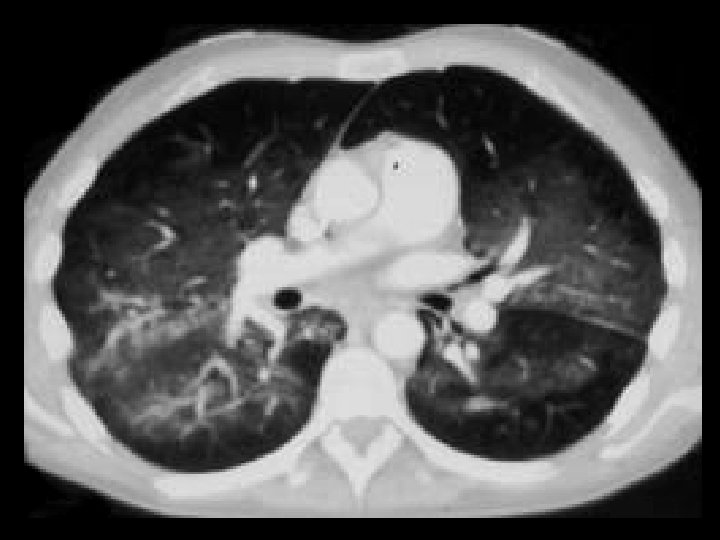

Pneumacystis pneumonia • Findings: – Bilateral ground glass opacity emanating from the hila – Normal underlying parenchyma • ddx: – Hypersensitivity pneumonitis – Usual interstitial pneumonia – Cryptogenic organizing pneumonia – Hemorrhage